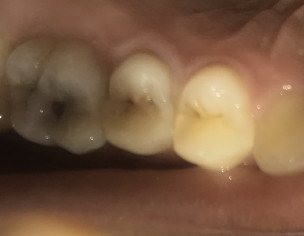

Aoa. I have extremely sensitive teeth I can’t Cold drink water. But nowaday there is a cavity in my molar that too sensitive to anything I eat or drink. I constantly have mild pain/sensitivity in my teeth. Also the teeth looks grey in colour. The x ray is attached below. What to do? The filling will do or RCT?

Hello. The X-ray is not very clear so no diagnosis can be made on the basis of X-ray. But judging by the looks of the cavity, filling might do. But again, no clear diagnosis as X-ray is not clear. For sensitivity, get scaling and poslisinh done. Also use sensodyne toothpaste.

Dear concerned with the picture it seems it will be saved with filling but x ray needs to be done again

without any delay get it done before its confirmed RCT case

Dear pain is subsiding immediately after cold stimulus. Most probably tooth might only need filling.  But if pain stays for long root canal treatment  will be needed. X ray not very good quality  so can't  comment on it. I will advise to visit dentist earliest.